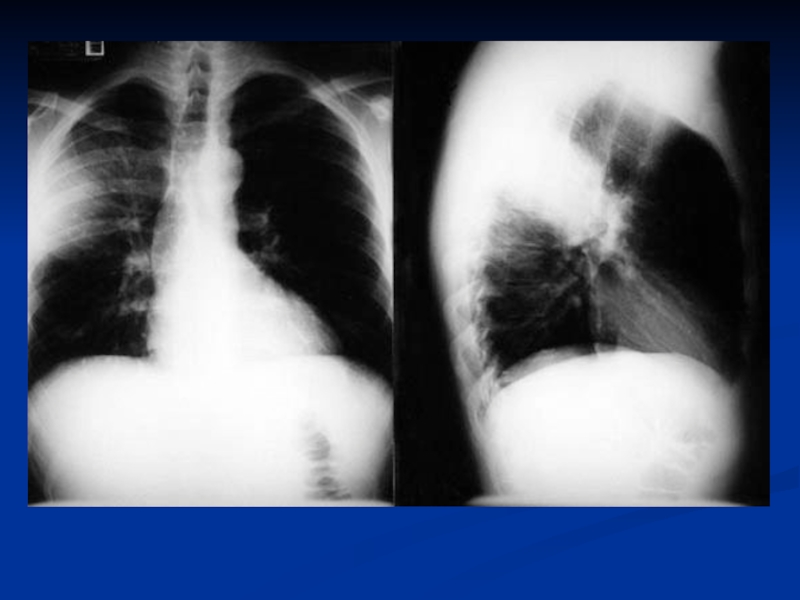

укорочение перкуторного звука в проэкции

инфильтрата;

гемограмма: нейтрофильный лейкоцитоз, сдвиг формулы влево;

рентгенограмма: инфильтраты легочной ткани, усиление легочного рисунка в перифокальных участках.

нарушение терморегуляции (гипер- или гипотермия, токсикоз);жесткое бронхиальное или ослабленное дыхание, через 3-5 дней присоединяются влажные хрипы;укорочение перкуторного